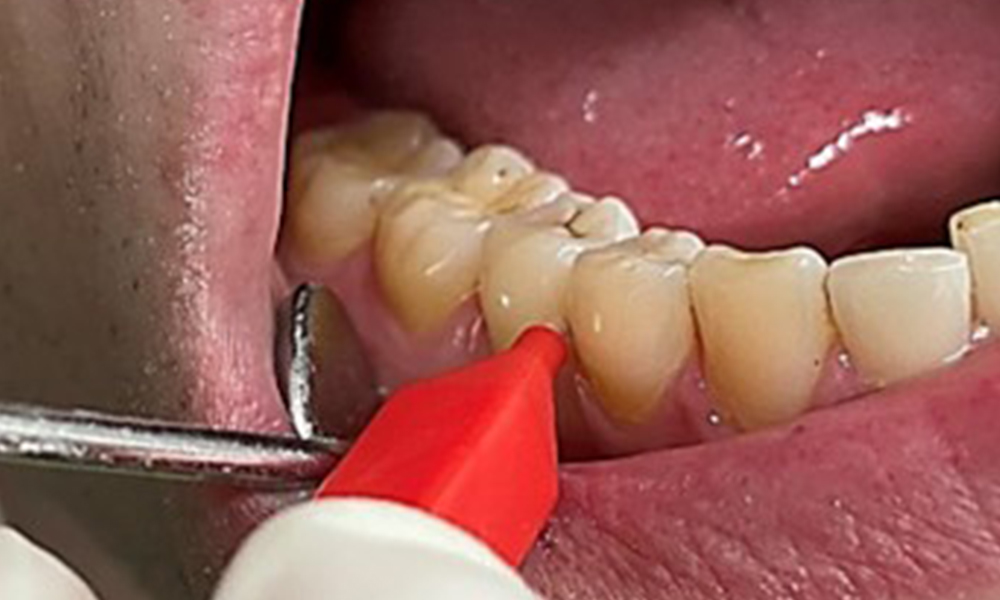

Close-up view of teeth

Fig. 5: Close-up view of teeth 45 to 47. The green arrows show dental attrition and erosions of the buccal cusps with partial enamel loss, © Dr R. Krapf

The patient has full dentition with a total of 28 teeth. There were noteworthy erosions and attritions. (Fig. 4, Fig. 5). Due to bruxism, the patient has been wearing a splint with an adjusted bite block at night for many years. The erosions were caused by long-term consumption of isotonic beverages. No periodontal bone loss or active caries were observed.